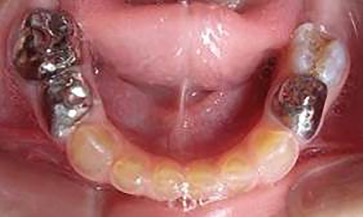

El examen clínico intraoral reveló alteración de la estructura y color de las piezas primarias, atrición y pérdida de la dimensión vertical (Figura 2). Radiográficamente se observó la presencia de coronas con marcada constricción cervical y raíces cortas (Figura 3). Presentaba alto riesgo cariogénico, por la presencia de lesiones de caries activas y dos restos radiculares, sumado a la anomalía estructural de la dentina (riesgo biológico específico) y bajo riesgo gingivoperiodontal. El riesgo socio-económico era alto por provenir de una familia con marcadas limitaciones económicas. Luego de la anamnesis, examen clínico y radiográfico, e interconsulta con el médico de cabecera se estableció el diagnóstico de DI Tipo I asociado a OI tipo I. Se planificó un tratamiento integral y preventivo con los objetivos de devolver forma y función, y proteger y evitar el desgaste de los tejidos conductas que pudieran interferir con el tratamiento.

Figura 2: Examen clínico intraoral del maxilar superior e inferior y vista anterior. Año 2007

Figura 4: Postoperatorias clínicas del maxilar superior e inferior (2007)